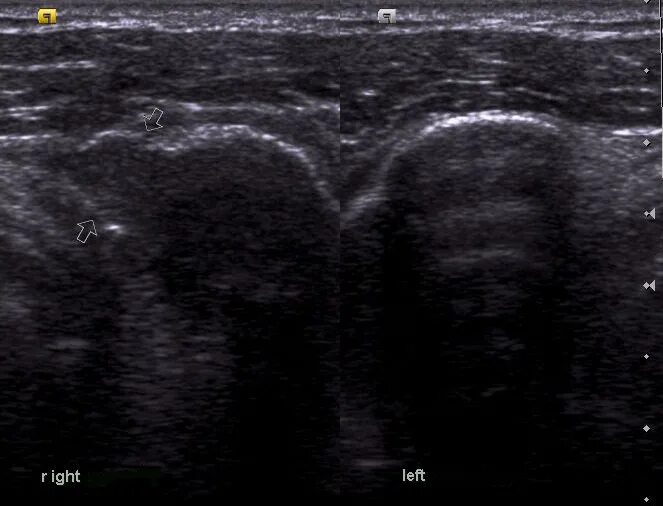

Метастазы рака почки